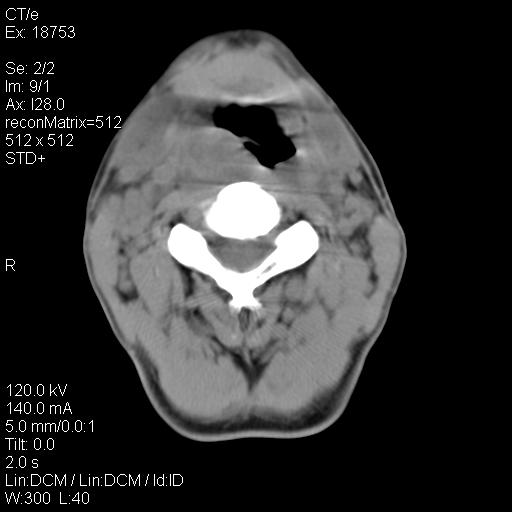

标题: CT21693:男 58岁 右侧咽部疼她2天余 PE:右侧扁桃体肿大 压痛 [打印本页]

标题: CT21693:男 58岁 右侧咽部疼她2天余 PE:右侧扁桃体肿大 压痛

右化脓性扁桃体炎症伴咽后壁脓肿形成.